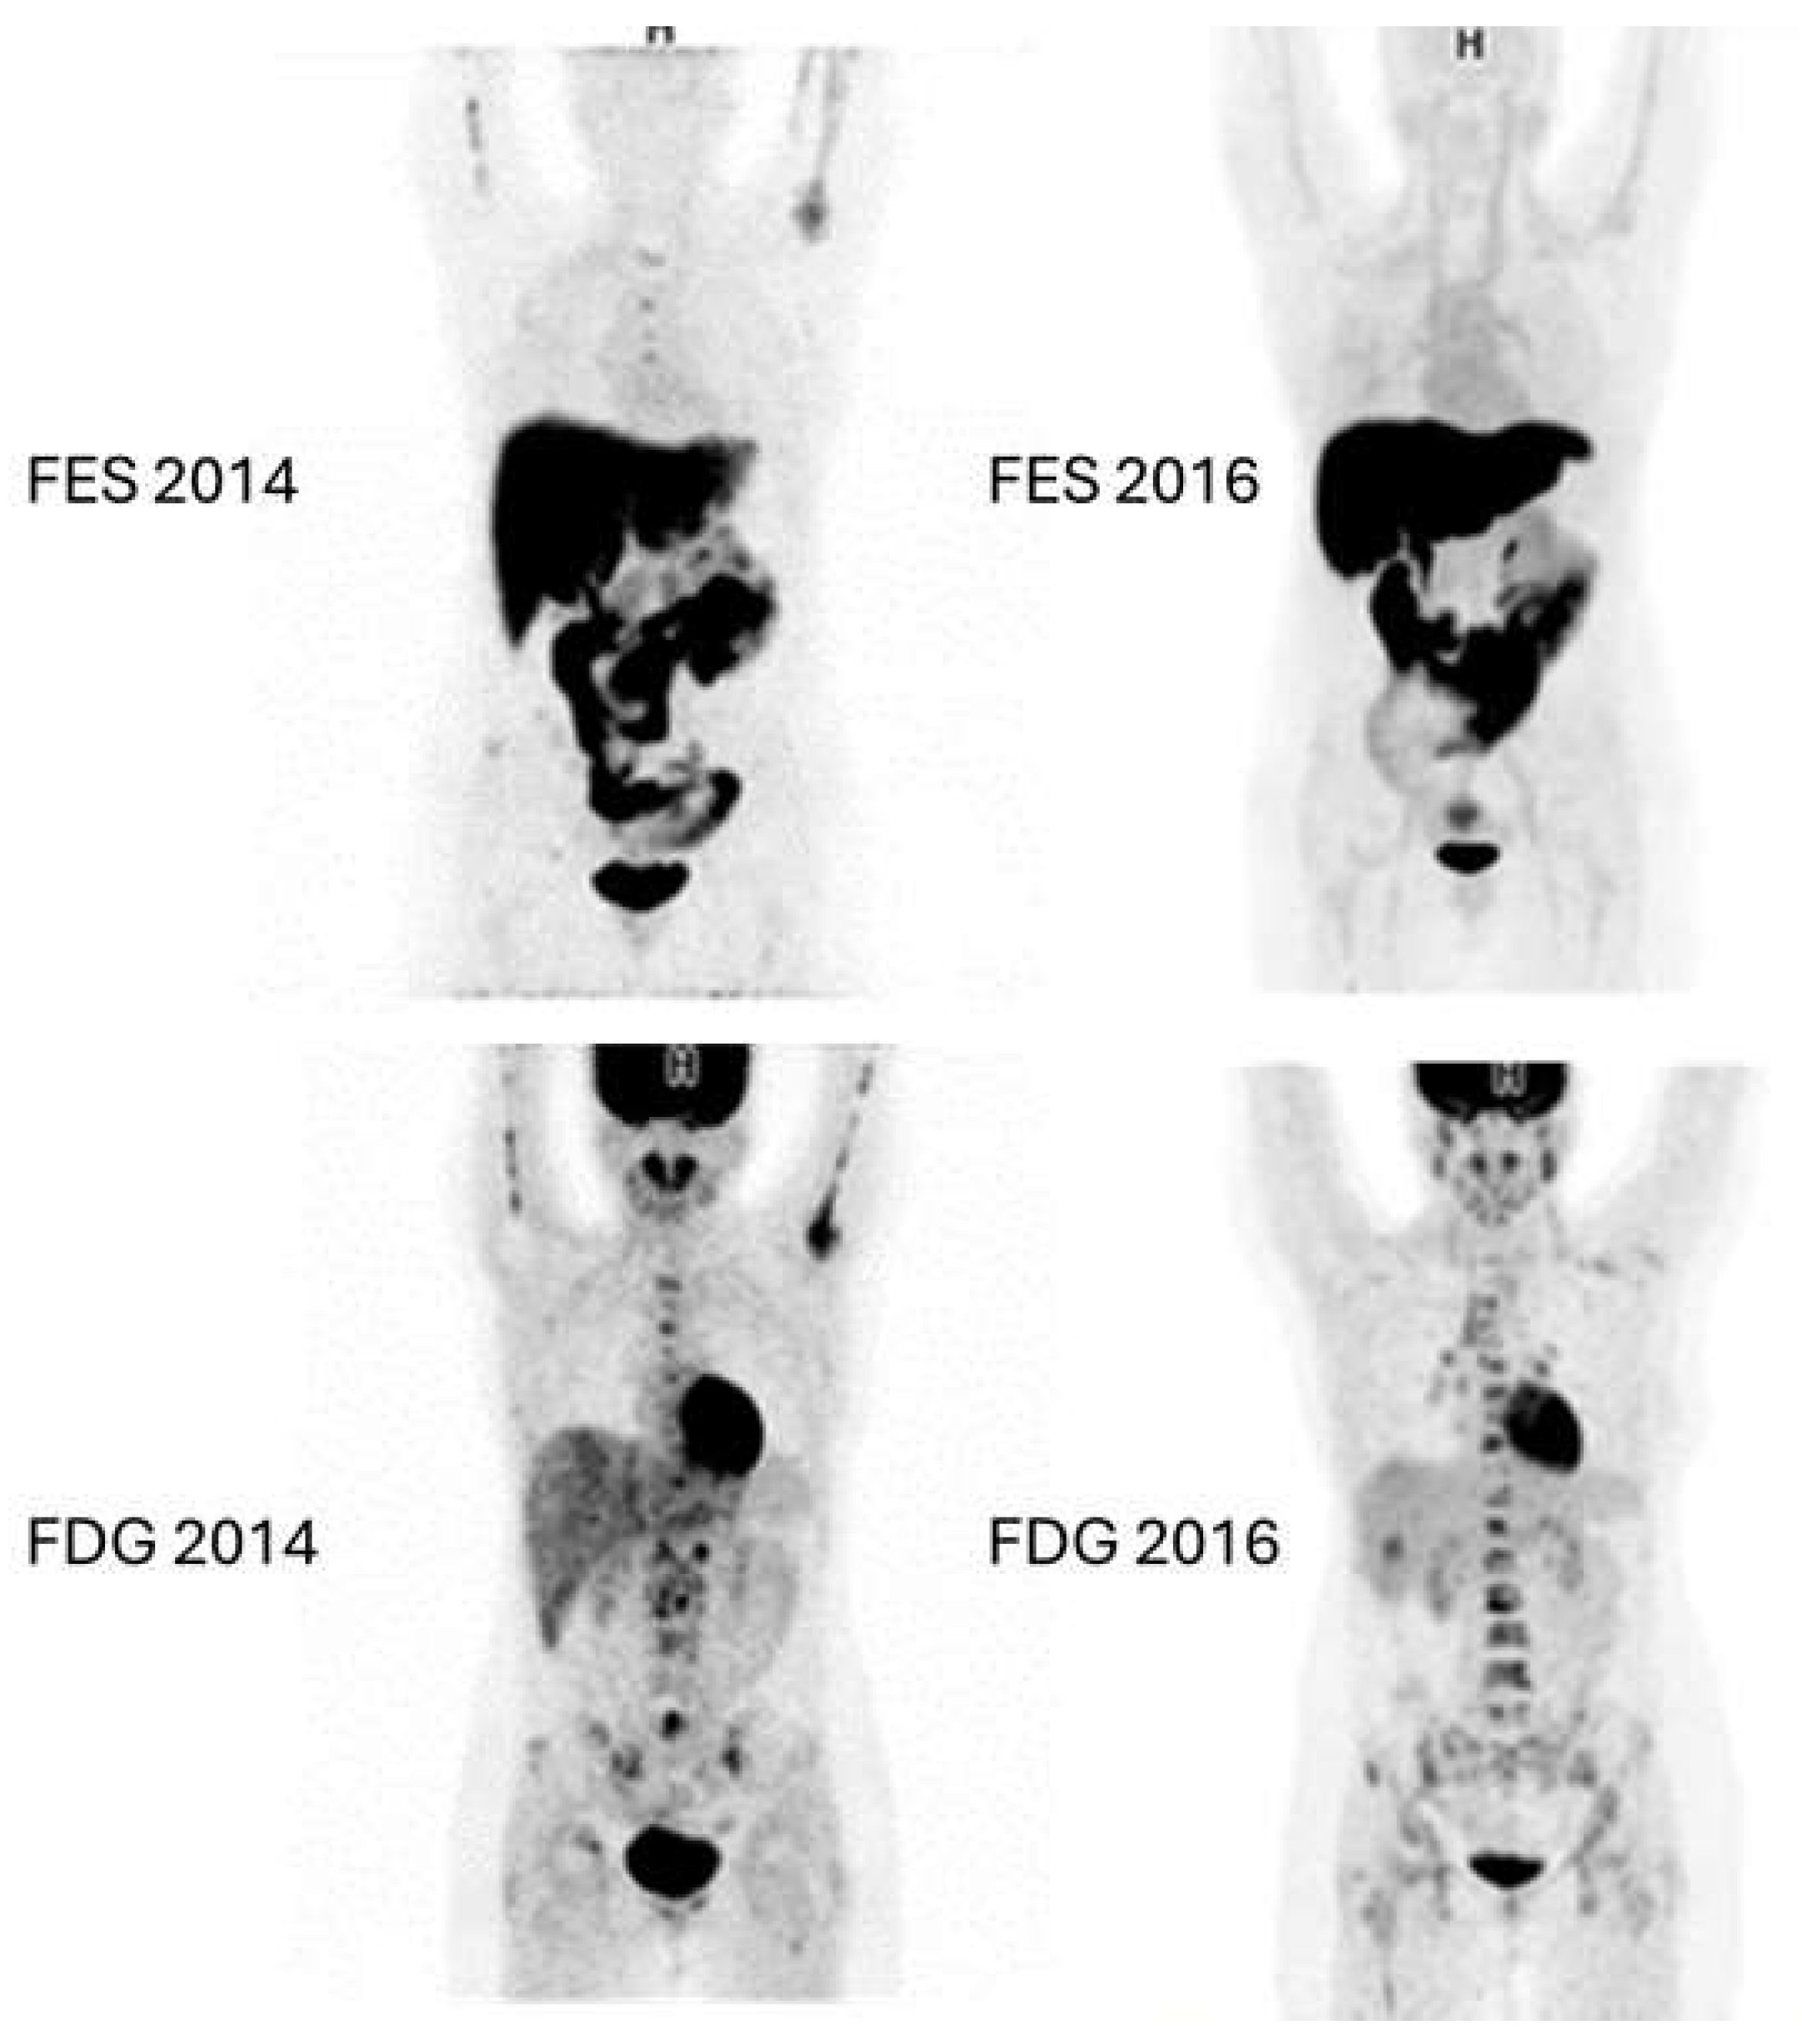

Figure 6 and Figure 7 show examples of images of breast cancer obtained using FES PET/CT.